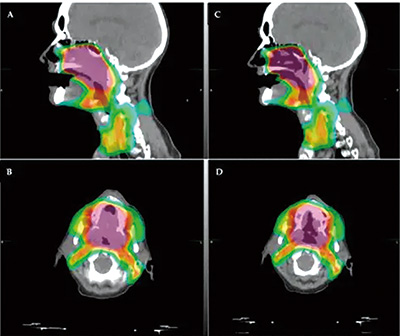

为了评估IMRT的头颈癌患者中放疗与嗅觉功能的相关性,包括嗅觉功能随时间的变化,该项非随机化临床试验招募了2021年1月1日至2023年12月1日组织学确诊并接受IMRT治疗的头颈癌患者。计划接受放疗的患者在多个时间节点接受TWSIT量表的嗅觉功能评估。鼻腔内镜用于排除混杂性的鼻腔疾病(如严重鼻中隔偏移、慢性鼻窦炎、头部外伤或头部放疗史)。主要终点为嗅觉评分与嗅觉区辐射剂量间的相关性。

结果显示,63例放疗前嗅觉功能正常的患者被纳入分析,其中位年龄为55岁(32~75岁),其中52例(82.5%)为男性。最常见的原发癌症部位为口腔和口咽(37例,58.7%),其次是鼻咽(16例,25.4%)。大多数患者患有晚期疾病(Ⅲ~Ⅳb期占79.4%)。根治性放疗占54%,辅助放疗占46%。

总体来看,放疗后嗅觉功能评分下降,部分患者在随访期间有部分恢复。小剂量放疗的患者通常保持稳定的嗅觉功能。放疗剂量与嗅觉功能障碍中度正相关。放疗剂量每增加1 Gy,TWSIT评分下降0.128(0.083~0.173)。受试者工作特征分析确定,22 Gy为估算嗅觉障碍的潜在阈值,此时曲线下面积为0.74(95%CI 0.52~0.96,P=0.03),敏感性为64%,特异性为92%。

在11例出现嗅觉功能障碍的患者中,5例的放疗剂量≤22 Gy,6例的剂量较大。多变量分析显示,嗅觉区域平均放疗剂量超过22 Gy是唯一的独立风险因素(OR=20.65,95%CI 2.60~164.35)。部分接受大剂量放疗的患者出现长达1年的持续性的嗅觉功能障碍。根据敏感性和特异性,嗅球部位放疗剂量≤22 Gy或有超过90%的概率避免嗅觉功能障碍。